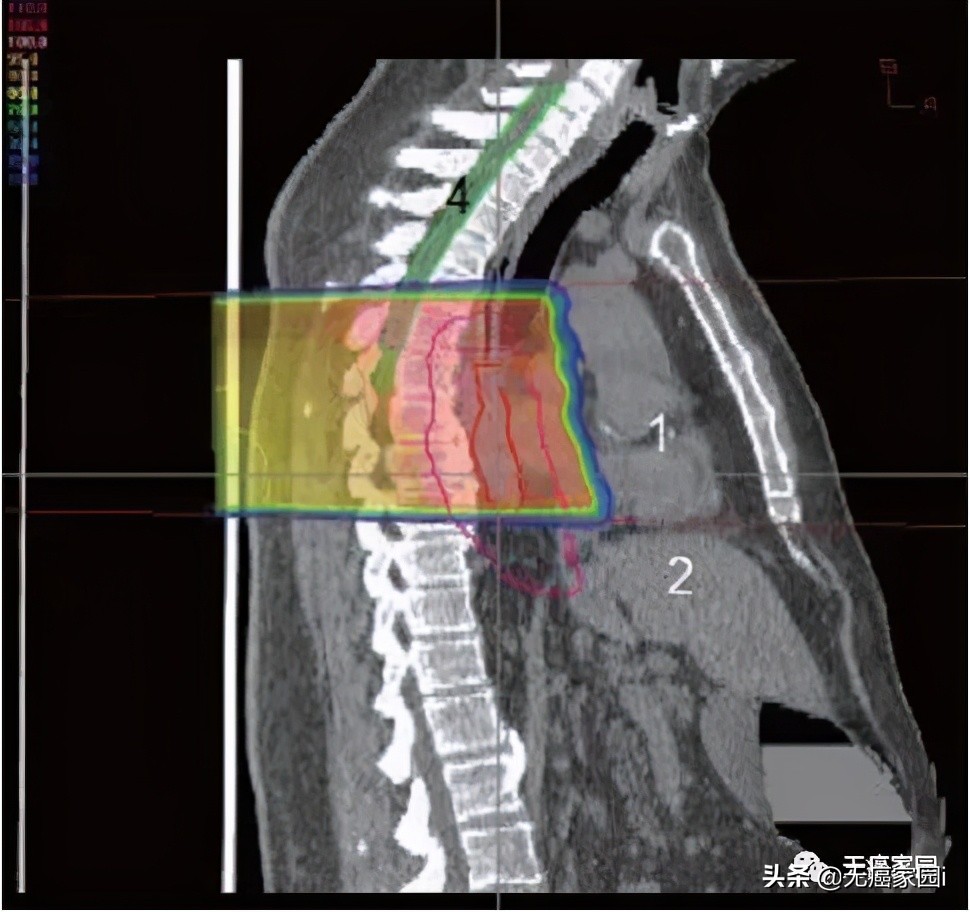

图2:后质子束进入人体并到达食道后停止的矢状图;1. 心;2. 肝脏;4; 脊髓

食道位于后纵隔内,靠近几个关键结构,即肺、脊髓和心脏。最大限度地减少对这些关键结构的毒性降低了患者的整体治疗发病率和死亡率。然而,必须在放射野中考虑足够大的边缘以覆盖肿瘤区域和受累淋巴结,这使周围器官面临更大的风险。肺剂量是食管癌放射期间毒性的主要危险因素。为了将脊髓剂量保持在容许范围内,通常需要使用多个倾斜角度的光束(图1~3)。这就导致肺部接收到大量辐射剂量,从而产生放射性肺炎和术后肺部并发症。

图1:治疗食道的后斜质子束的轴向视图。到达食道后,剂量立即下降,这最大限度地减少了心脏和肺接受的辐射剂量;1. 心;2. 肝脏;3. 肺;4. 脊髓